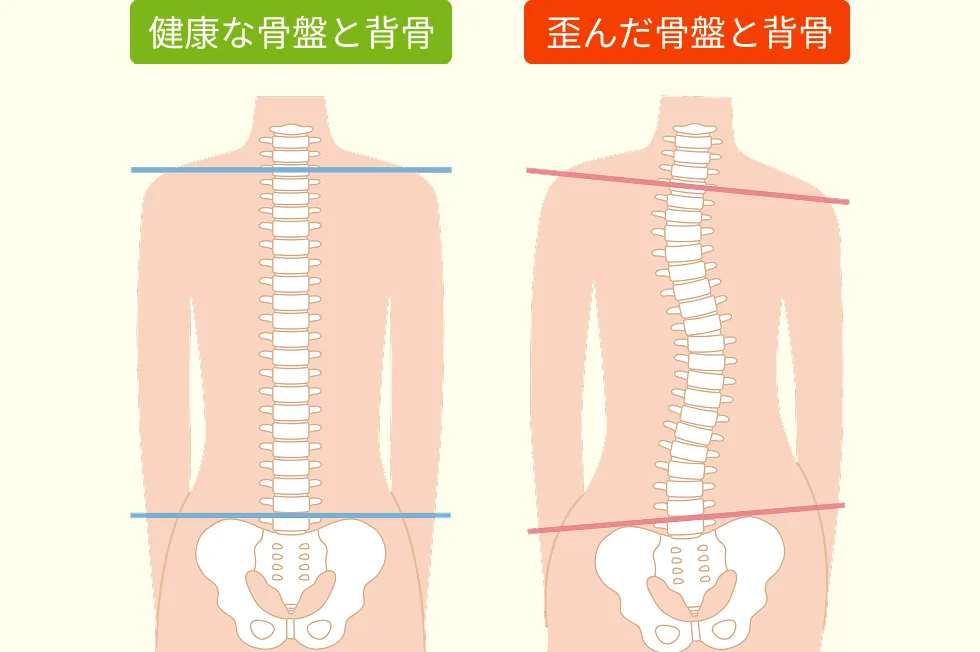

当院では痛い所だけを施術するのではなく、お一人お一人に合わせて脊柱管狭窄症の根本原因の箇所を見極め、そこに施術することで、根本的に脊柱管狭窄症を改善に導きます。特に根本的に良くするのに必要なのは背骨と骨盤の動きを良くすることです。

背骨と骨盤の動きが良くない箇所を見極め、そこを改善することにより脊柱管狭窄症は良くなっていきます。

背骨と骨盤の動きを良くすることで、背骨の中を通る、脊柱管が本来の状態になり、脊柱管狭窄症の根本的な改善に向かいます。

02:骨盤と背骨を整えるスペシャリストです。

一般的な整体院や整骨院では、骨盤は左右を整えれば良いと思っていますが、本当はそうではありません。

内臓をみても分かるように、体は左右が対称には出来ていません。それは骨盤もしかりです。

骨盤の左右の違いを使い分け、それぞれにアプローチをかけることで、骨盤を本来のあるべき位置へ戻します。

骨盤と背骨のゆがみをなくし本来の姿勢を取り戻して頂くことが症状の改善にはとても重要です。